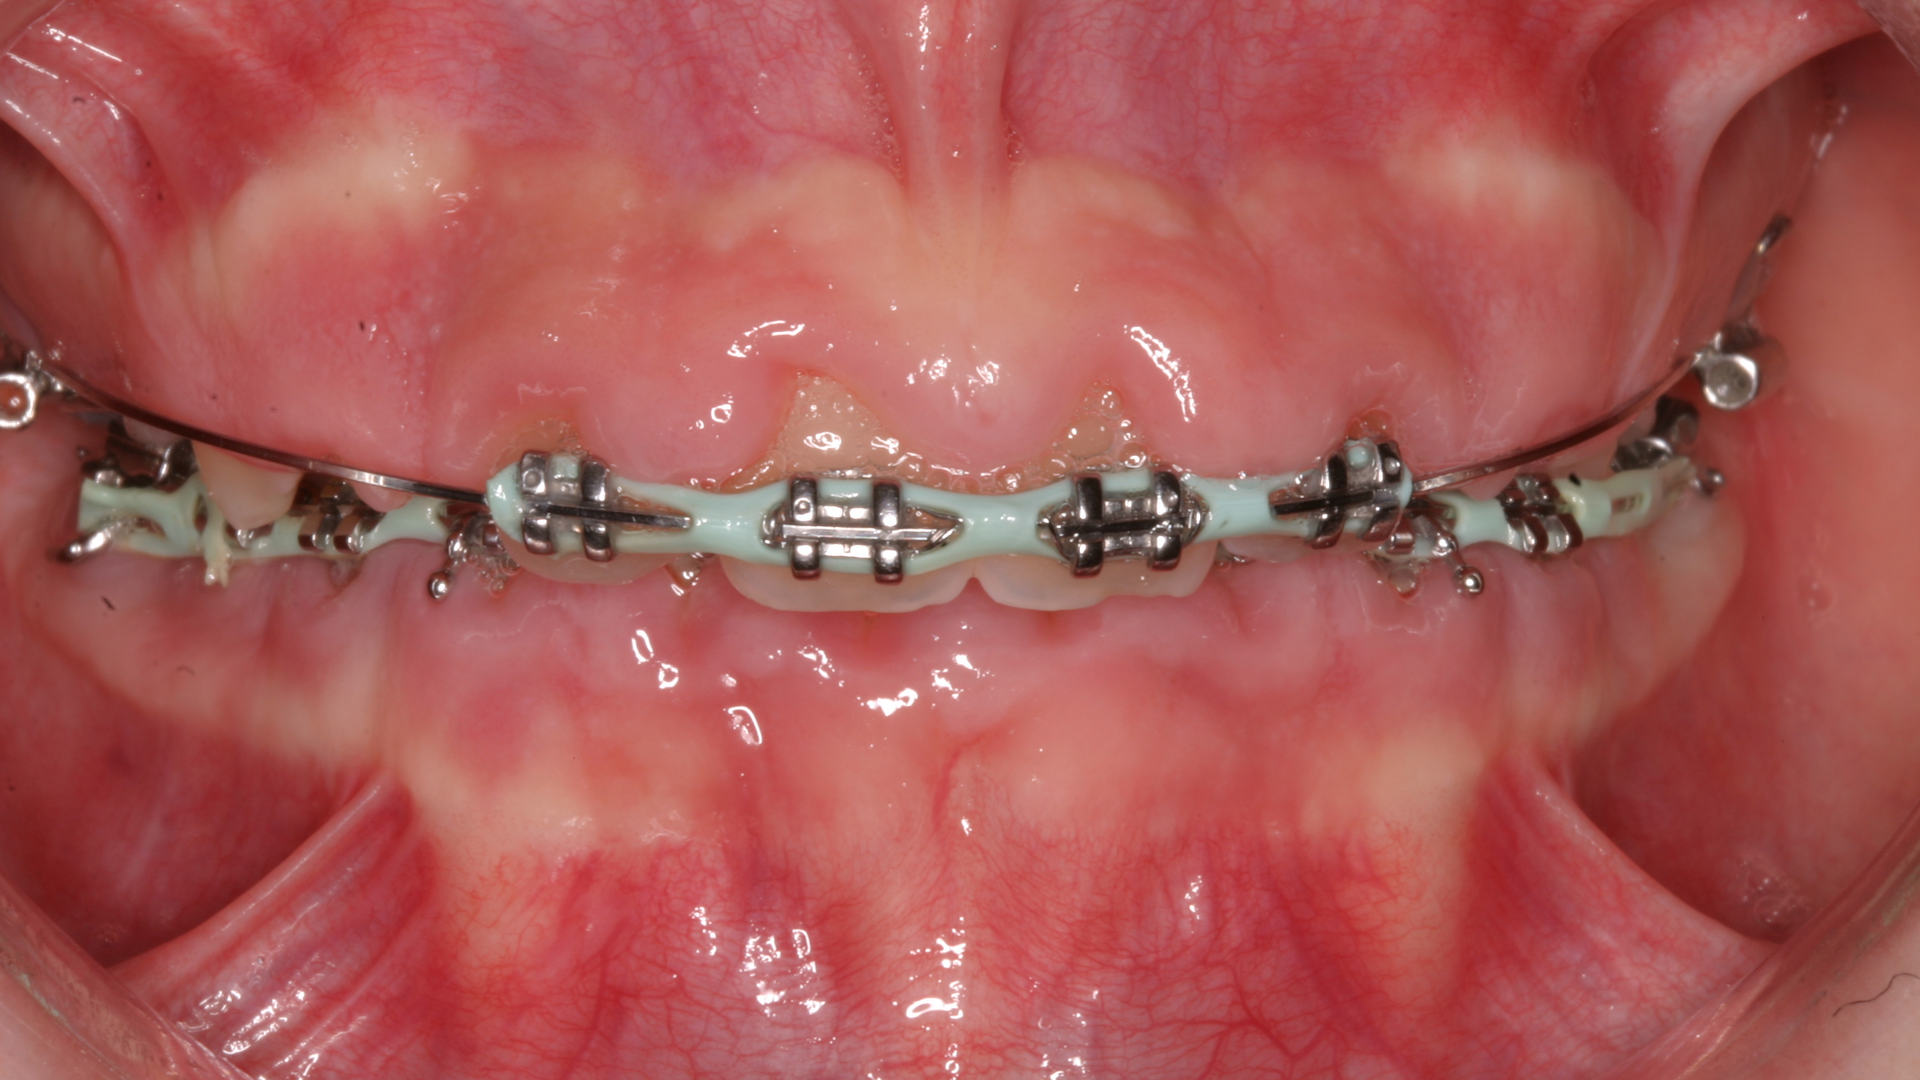

One reason people develop gummy smiles is inflammatory-induced gingival enlargement, typically caused by biofilm (bacteria) and the host response. Gum disease (gingivitis and periodontitis) can result in gum tissue swelling, redness, gum overgrowth, and bleeding (figure 1). In addition to bacterial infiltration of the gums due to poor oral hygiene, orthodontic appliances have been associated with gingival enlargement since braces can act as food traps (figure 2).Further reading: Considerations when using veneers to fabricate a perfect smile

Another laser that has been used to treat gingival enlargement and gummy smiles is a 9.3 micron CO2 laser (Solea from Convergent Dental; figure 2a). Unlike other lasers, the Solea laser has the capabilities of removing both soft and hard tissue, precise cutting accuracy due to control of both laser beam power and size, and the ability to cauterize inflamed tissue (figures 4c and 4d). Conventional instrumentation—such as blades, knives, and high-speed burs—can often lead to bleeding after surgical removal when the tissue is inflamed. With this type of CO2 laser, sutures and/or surgical dressing are often not needed.